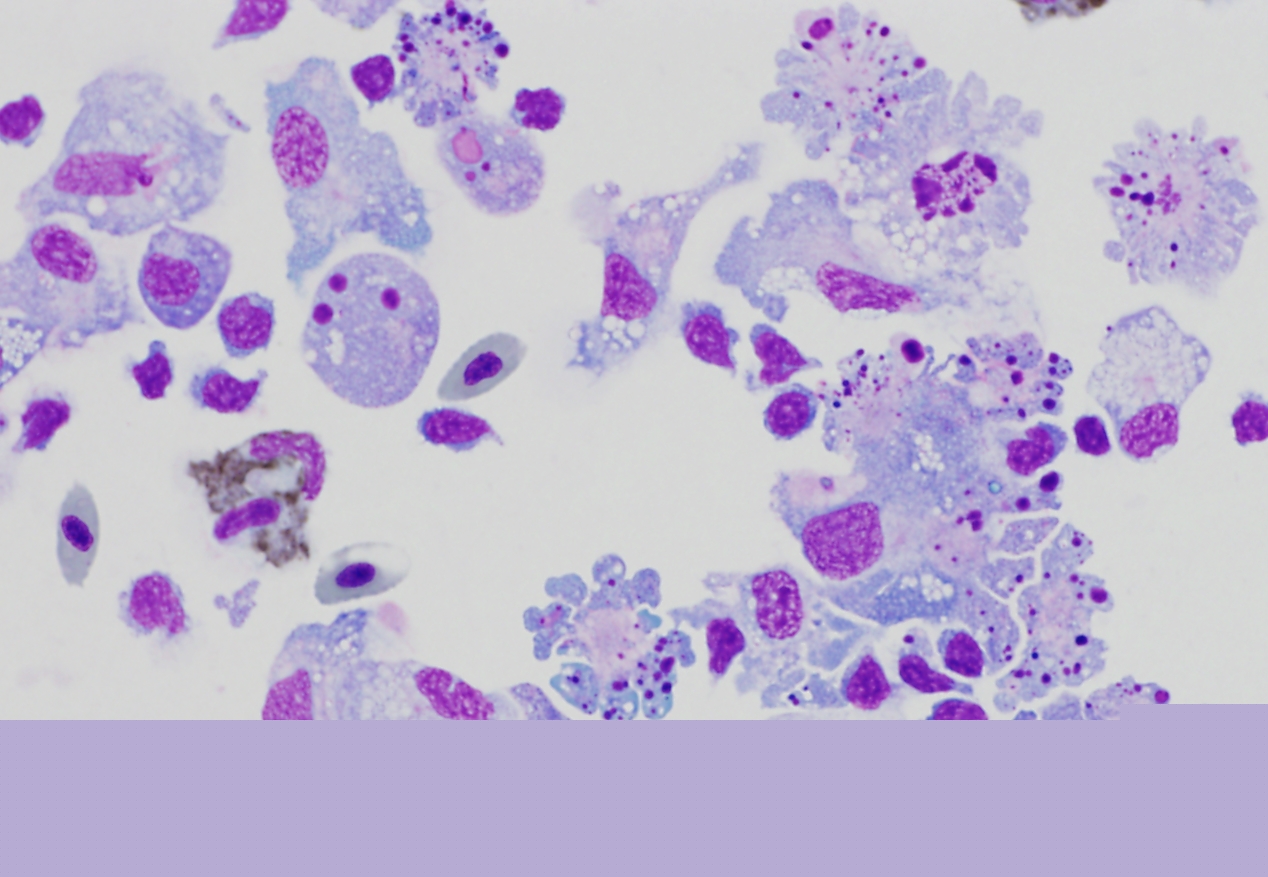

Fotografias ao microscópio de células a morrer, por apoptose, em consequência de exposição à toxina AIP56